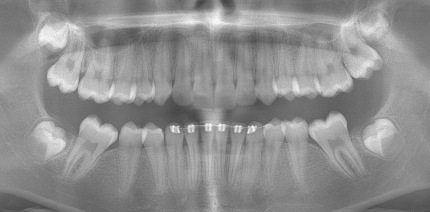

Patienten mit kieferorthopädischen (KFO-)Apparaturen gelten als potenzielle Kariesrisikopatienten, so das aktuelle Konsensuspapier „White...

Patienten mit kieferorthopädischen (KFO-)Apparaturen gelten als potenzielle Kariesrisikopatienten,...